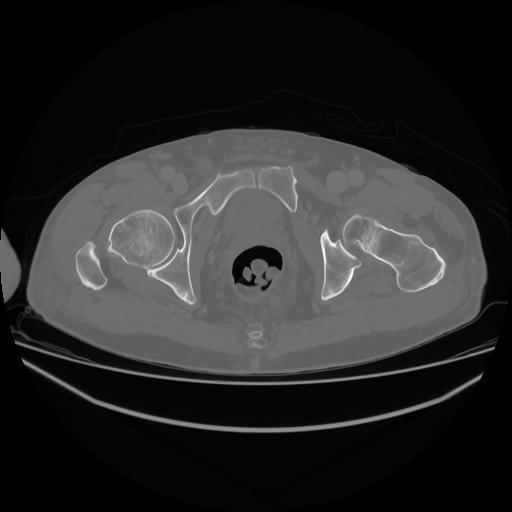

5 CUERPO,CE,Vol,1.0,CUERPO,,